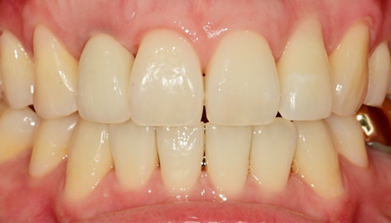

Before Treatment

After extraction, precise placement using surgical guide followed by pre-fabricated abutment connection

After extraction, precise placement using surgical guide,

followed by connection of

pre-fabricated abutment

Prosthesis completed on the day of surgery

Prosthesis completed on surgery day

After 2 months, replaced with final prosthesis if gingival contour changes or as needed

After 2 months, if gingival contour changes

or as needed, replaced with final prosthesis

Final Implant Results

BEFORE/AFTER

BEFORE

AFTER